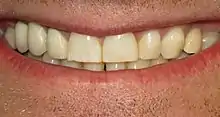

تلون الأسنان

تلون الأسنان (يسمى أيضا تصبغ الأسنان) هو لون غير طبيعي يحدث للأسنان.تلون الاسنان يمكن ان يحدث بسبب تراكم البقع على سطح الأسنان وهذا ما يسمى بالتصبغ الخارجي. أما الداخلي فيعود إلى امتصاص جسيمات بها صبغة إلى بنية الأسنان. هناك عدة عوامل مختلفة مسؤولة عن تلون الاسنان.[1]

علاج التصبغ

تغيير لون الأسنان الأمامية يعتبر السبب الأكثر شيوعا الذي يجعل الناس تسعي لرعاية أسنانها.ومع ذلك، كثير من الناس تطلب اسنان ناصعة البياض حتى مع وجود لون أسنان طبيعي. علاج تصبغ الأسنان يعتمد على معرفة السبب.[11] معظم تلون الاسنان غير ضار وقد يكون أو لا يكون ذات أهمية تجميلية للفرد. ولكن في حالات أخرى قد يشير إلى وجود علة باللب.